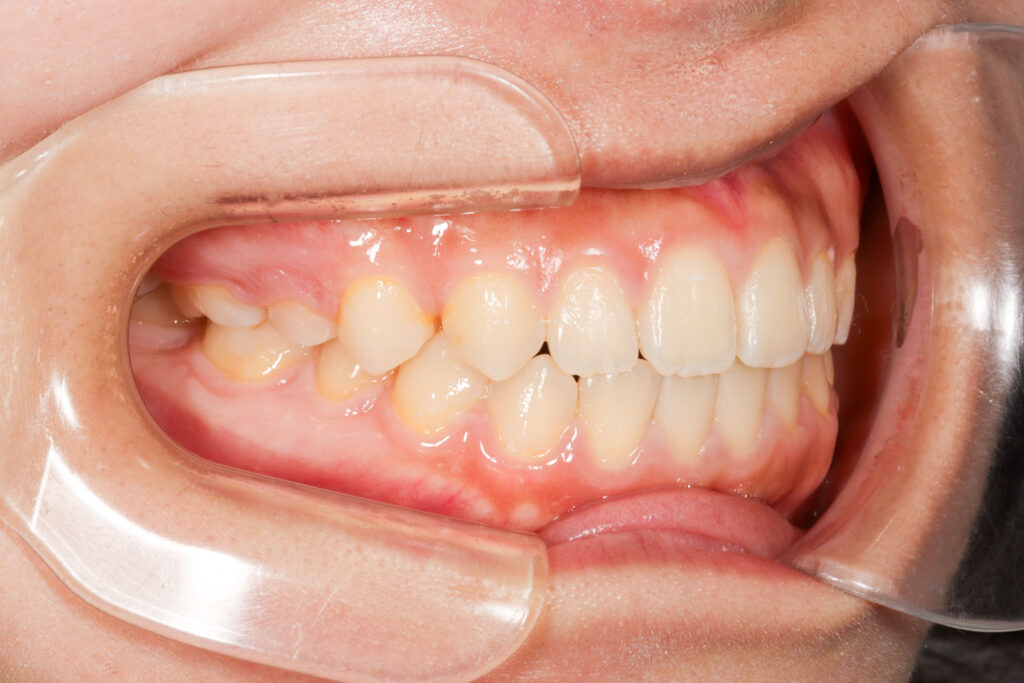

Before

After

年齢 10代

治療装置 上は裏側の矯正装置(ハーフリンガル)

治療内容 上下左右4本抜歯

治療期間 2年8か月

リスク 歯の移動に伴う痛み、歯肉退縮、歯根吸収、歯肉炎、虫歯

主訴 八重歯が気になる

症状 叢生(ガタガタ)

治療回数 33回程度

総額費用 125万円程度